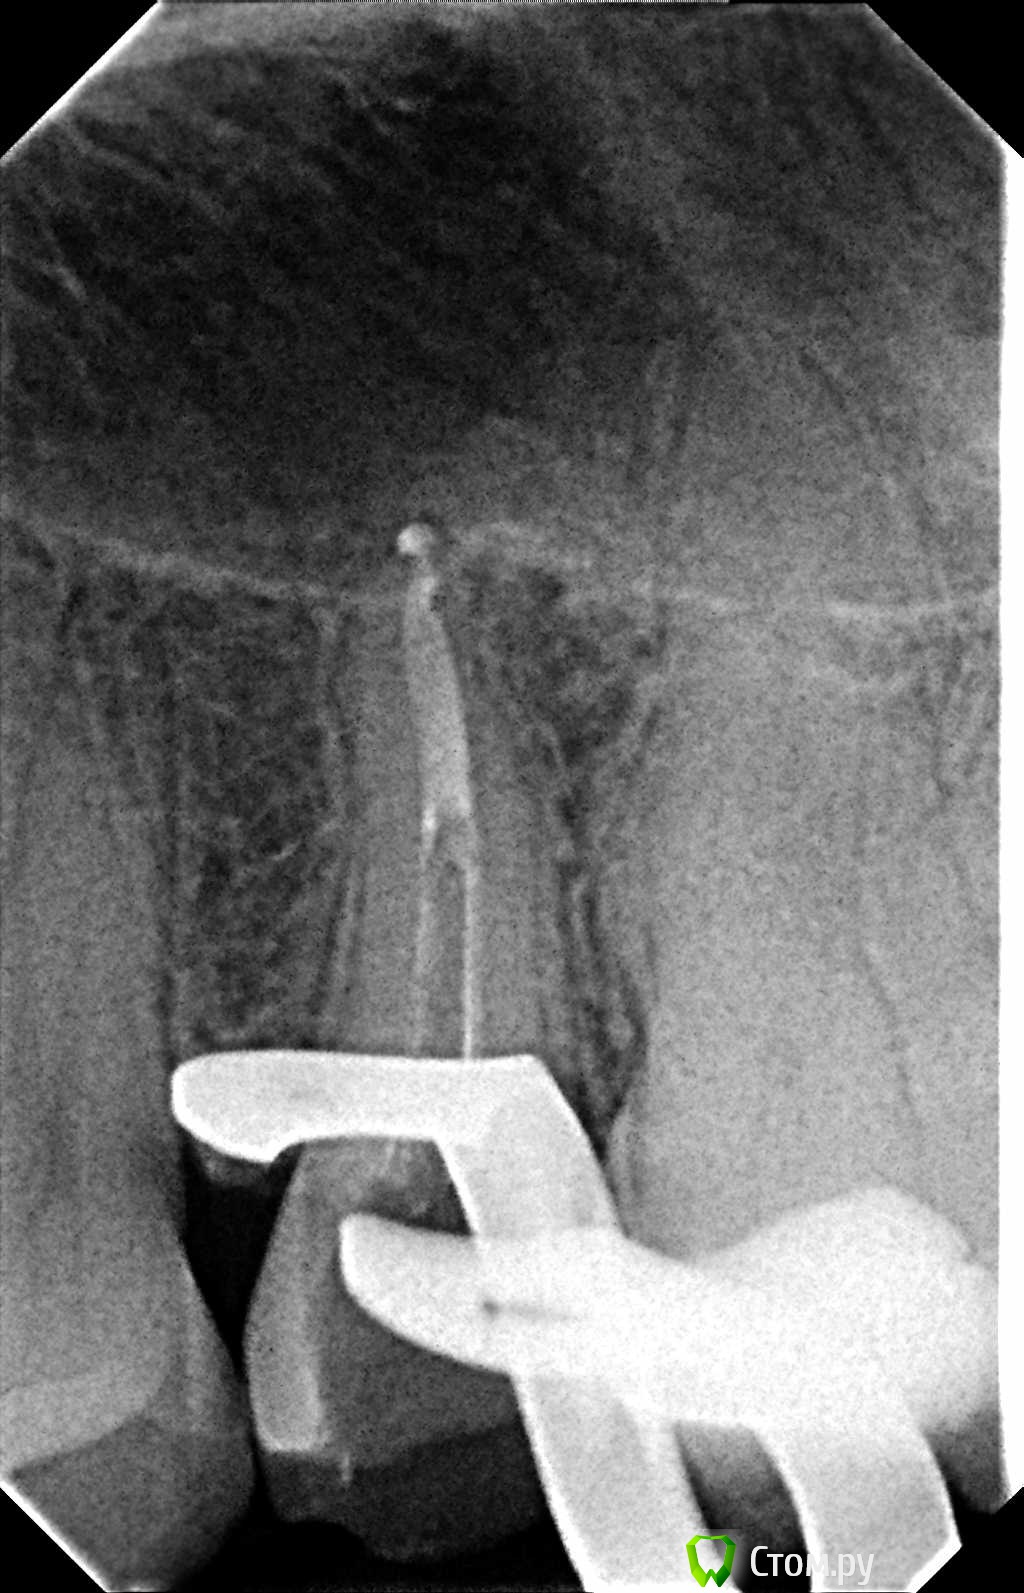

Hans85 Опубликовано 9 января, 2014 Автор Поделиться Опубликовано 9 января, 2014 (изменено) Так теперь попробуем выстроить нормальную логическую цепочку.Кейс из разряда сам сломал сам доставай-благо канал относительно прямой,времени удаление фрагмента заняло 15-20 минут.Сломал кстати протейпер S2 Изменено 9 января, 2014 пользователем Hans85 8 Ссылка на комментарий

Shaid Опубликовано 9 января, 2014 Поделиться Опубликовано 9 января, 2014 (изменено) Hans85, как извлекли инструмент? Судя по апексу - был риск протолкнуть отломок за апекс. Клевый кейс! Изменено 9 января, 2014 пользователем Shaid Ссылка на комментарий

Hans85 Опубликовано 9 января, 2014 Автор Поделиться Опубликовано 9 января, 2014 Hans85, как извлекли инструмент? Судя по апексу - был риск протолкнуть отломок за апекс. Клевый кейс! Сделал минимально пространство в области торца инструмента 15 U-File чуть расшатал и с водой озвучивал рассчитывая на гидроудар. Ссылка на комментарий